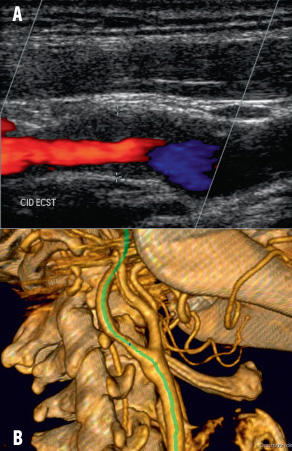

Fig 2

Imagerie d’une sténose

A. Echo-doppler montrant une plaque hypoéchogène ; B. Angio-CT montrant une sténose de l’ordre de 60 %.